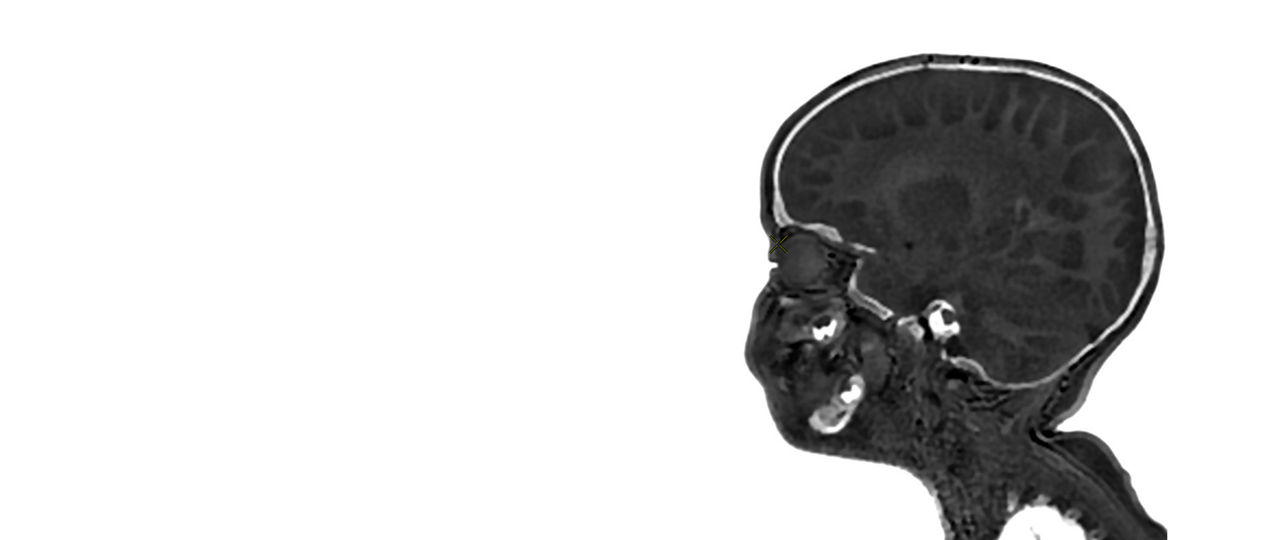

Pediatric MRI for SIGNA™

Specialized pediatric MRI protocols specifically designed to meet the needs of your smallest, most fragile patients. Provide ease of use for technologists and clinical excellence for clinicians.

Clinical Pediatric MRI

Pediatric MRI imaging applications

Precision and personalization